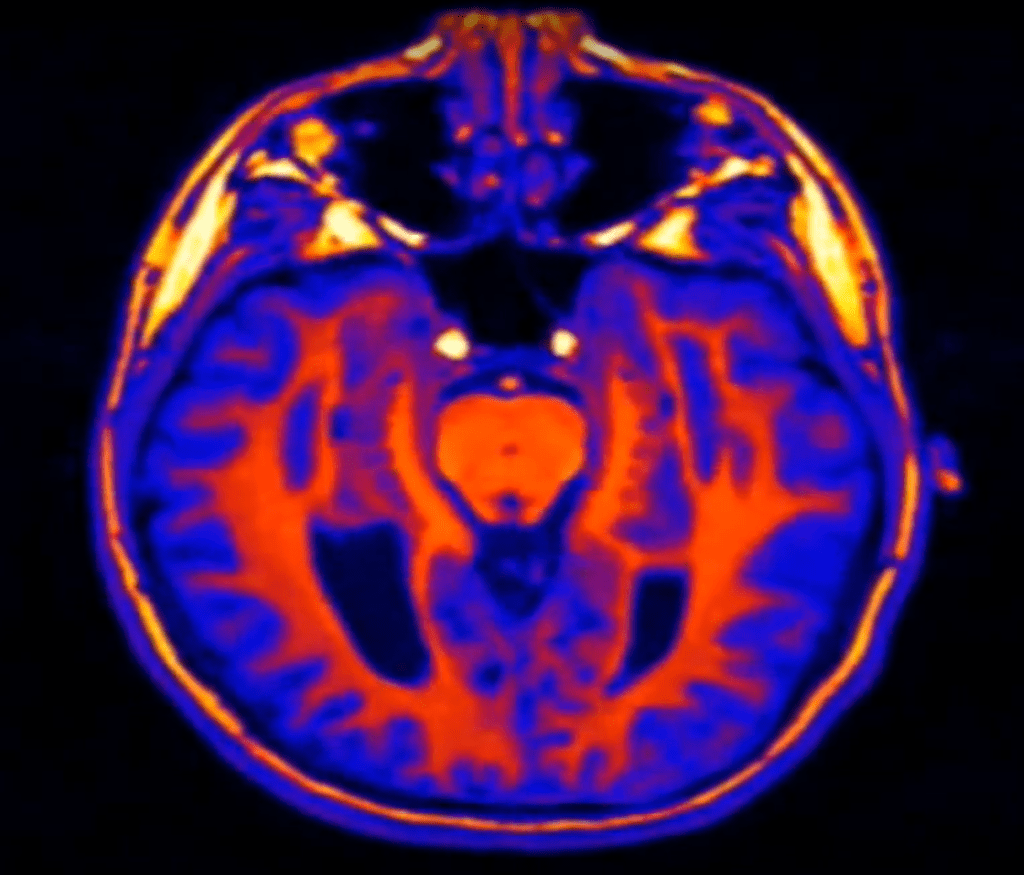

Nach diesem retardierenden Moment gibt es kein Halten mehr. Mae wird zum Superstar des Unternehmens. Ihre Freundin Annie neidet ihr den Erfolg und stürzt sich in ein anderes Firmenprojekt, das ihr psychisch schwer zu schaffen macht. Schließlich wird sie krank und fällt ins Koma. Am Ende des Romans besucht Mae ihre Freundin im Krankenhaus. An die Geräte angeschlossen, liegt Annie auf dem Bett. Auch ihre Gehirnaktivitäten werden gemessen, sie erscheinen auf den Monitoren als „Farbexplosionen“, „…aber was genau in ihrem Kopf vor sich ging, wusste keiner, und das ärgerte Mae irgendwie.“ Immer stärker wird dieses Gefühl bei ihr, bis sie sich schließlich entscheidet, das Problem bei der nächsten Sitzung im „Circle“ zur Sprache zu bringen.

Die gute Nachricht: Auf „The Circle 2.0“, das Streamen von Gedanken, wird die Welt noch lange warten müssen, wenn es überhaupt je möglich sein wird. Dem stehen zunächst gigantische technische Probleme im Wege. Teile der Presse und einzelne Vertreter der Hirnforscherzunft erwecken ja mitunter der Eindruck, die Wissenschaft werde in absehbarer Zeit in der Lage sein, Gedanken per „Hirnscan“[i] zu lesen. Nichts könnte indes weiter von der Wahrheit entfernt sein. Die bei „Hirnscans“ produzierten bunten Bildchen mit angefärbten Hirnregionen haben sicher ihren wissenschaftlichen Wert. Mit Gedankenlesen haben sie indes nicht mehr zu tun, wie ein Stück Geigenholz mit der 5. Symphonie von Beethoven. Diese Abbildungen sind nämlich mit Nichten Momentaufnahmen eines Gehirns, sondern sie entstehen in einem langwierigen Prozess, der Monate dauern kann. So muss beispielsweise das „Hintergrundrauschen“ des Gehirns herausgefiltert werden, indem man von einem „Hirnscan“ bei einer bestimmten Aktivität einen anderen Scan ohne Aktivität subtrahiert (Differenzbild). Danach folgt noch eine Kaskade von messtechnischen und statistischen Bearbeitungen. Und oft werden die Messungen von vielen Personen gemittelt, so dass die Bilder ohnehin nur ein Durchschnittsgehirn darstellen (mehr dazu hier).

Doch selbst, wenn es möglich wäre, Schnappschüsse des Gehirns im (Milli-)Sekundentakt herzustellen, stünde man vor der Frage, ob eine Abfolge solcher Scans einem bestimmten Gedanken entspricht und damit in diesen übersetzbar ist. Bejaht man diese Annahme, wäre jeder Gedanke identisch mit einer Abfolge bestimmter neuronaler Prozesse und damit vollständig durch diese erklärbar (Identitätstheorie). Wer diese Annahme bejaht, steht allerdings vor zwei schwierigen Problemen.